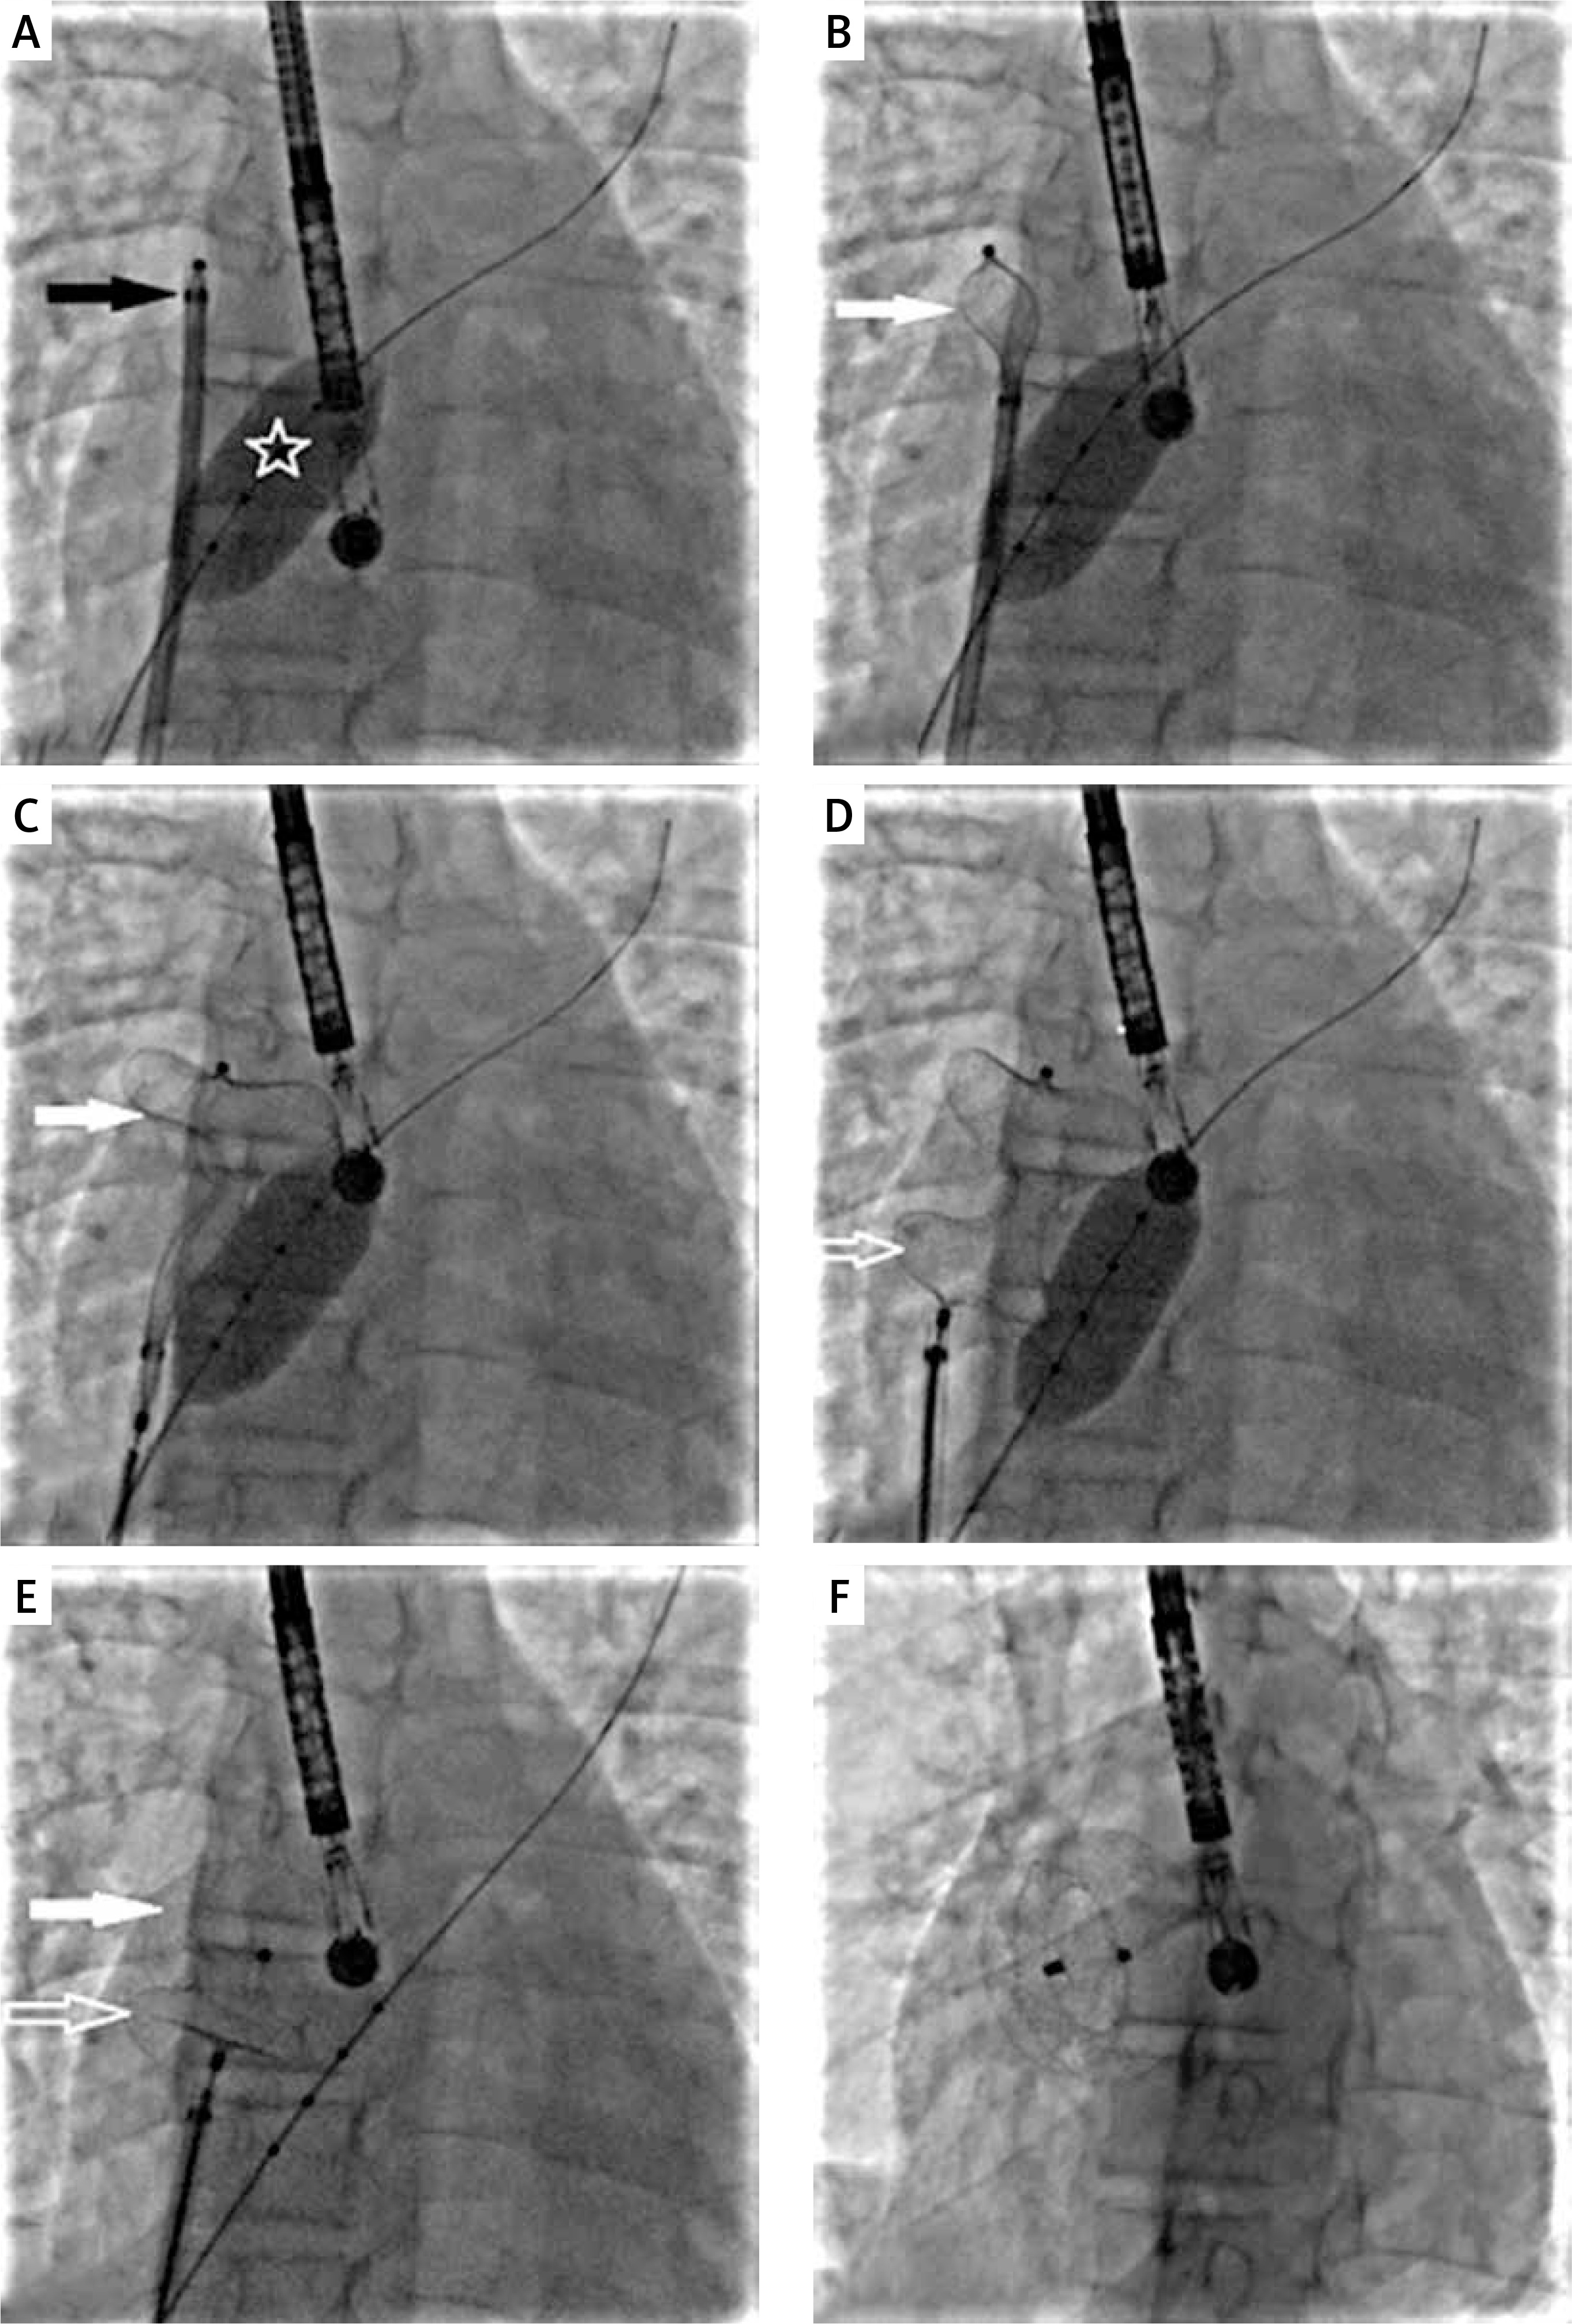

A 30-mm Amplatzer Septal Occluder (Abbott) mounted on a classic delivery cable was introduced via a standard 10 Fr TorqueVue sheath (Abbott); however, due to the large size of the defect and deficient rims, a stable implant position was not obtained. The left atrial disc slipped across the defect to the right atrium. Through an additional femoral vascular access, a 25-mm diagnostic sizing balloon catheter (NuMed) was inserted into the defect. Next, the balloon was simultaneously inflated (Figure 2 A) and the left atrial disc was deployed starting in the right upper pulmonary vein (Figures 2 B, C) followed by deployment of the right atrial disc (Figures 2 C, D). With stable device position the balloon was deflated (Figures 2 E) and gently withdrawn. After echocardiographic confirmation of the optimal position of the occluder and unobstructed flow from the superior vena cava, the device was released (Figure 2 F). With a combination of 2 modified techniques the device was deployed successfully in the first attempt.

Figure 2

Percutaneous large secundum atrial septal defect closure with combination of modified techniques. A – A sizing balloon (white star) is inflated with the long sheath and the occluder (black star) ready for deployment in the right upper pulmonary vein. B – The left atrial disc (white arrow) being deployed in the right upper pulmonary vein. C – The left atrial disc (white arrow) fully deployed with the sizing balloon inflated. D – The right atrial disc (white empty arrow) deployed with sizing balloon inflated. E – Gradual deflation of the sizing balloon after both discs have been deployed and progressive conformation of the discs (white arrows) as the balloon is completely deflated. F – Final position of the device after release